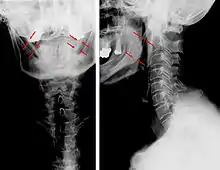

Radiograph, lateral view showing elongated stylohyoid process and stylohyoid ligament ossification

Radiograph, lateral view showing joint-like formation in ossified stylohyoid ligament

CT scan, coronal section showing bilateral extended styloid process and stylohyoid ligament ossification (incidental finding)

Diagnosis is suspected when a patient presents with the symptoms of the classic form of "Eagle syndrome" e.g. unilateral neck pain, sore throat or tinnitus. Sometimes the tip of the styloid process is palpable in the back of the throat. The diagnosis of the vascular type is more difficult and requires an expert opinion. One should have a high level of suspicion when neurological symptoms occur upon head rotation. Symptoms tend to be worsened on bimanual palpation of the styloid through the tonsillar bed. They may be relieved by infiltration of lidocaine into the tonsillar bed. Because of the proximity of several large vascular structures in this area this procedure should not be considered to be risk free.

Imaging is important and is diagnostic. Visualizing the styloid process on a CT scan with 3D reconstruction is the suggested imaging technique.[12] The enlarged styloid may be visible on an orthopantogram or a lateral soft tissue X ray of the neck.